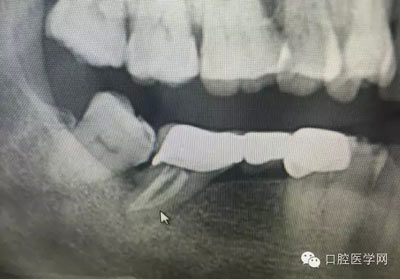

這是一例外院樹脂修復后十個月出現(xiàn)牙髓炎癥狀的患者。遇到這樣子的患者大家會怎么做,證明選擇,還有就是可做可不做治療的如何去平衡。